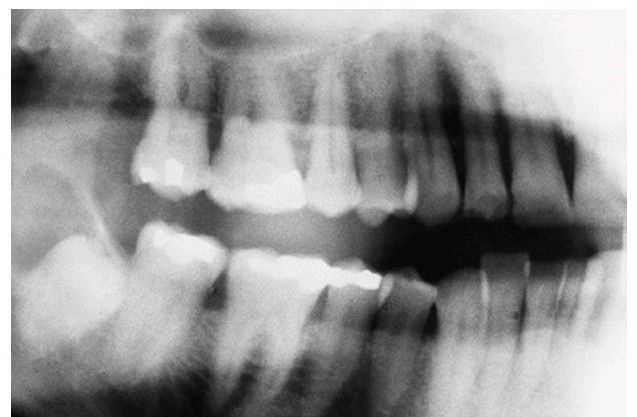

Dentigerous cyst

Small dentigerous cyst arising around an impacted tooth.